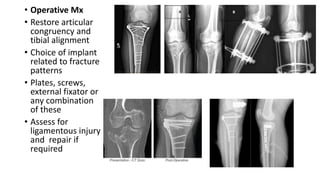

• Operative Mx

• Restore articular

congruency and

tibial alignment

• Choice of implant

related to fracture

patterns

• Plates, screws,

external fixator or

any combination

of these

• Assess for

ligamentous injury

and repair if

required